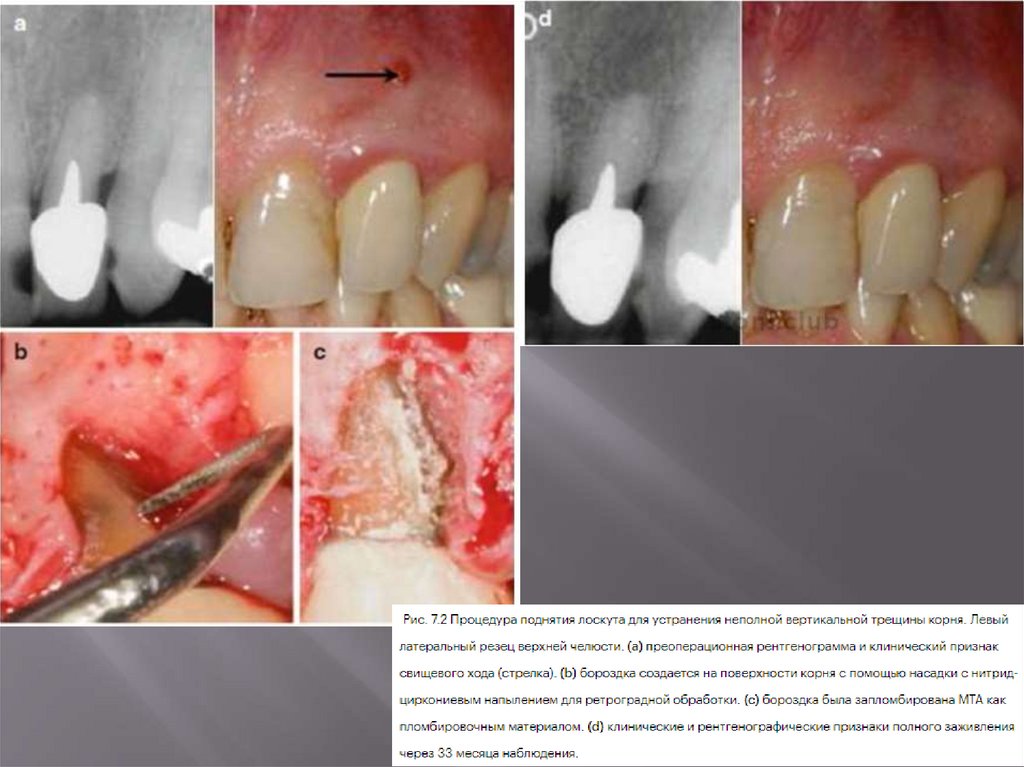

6.7.3. Поднятие лоскута и пломбирование трещины корня

81